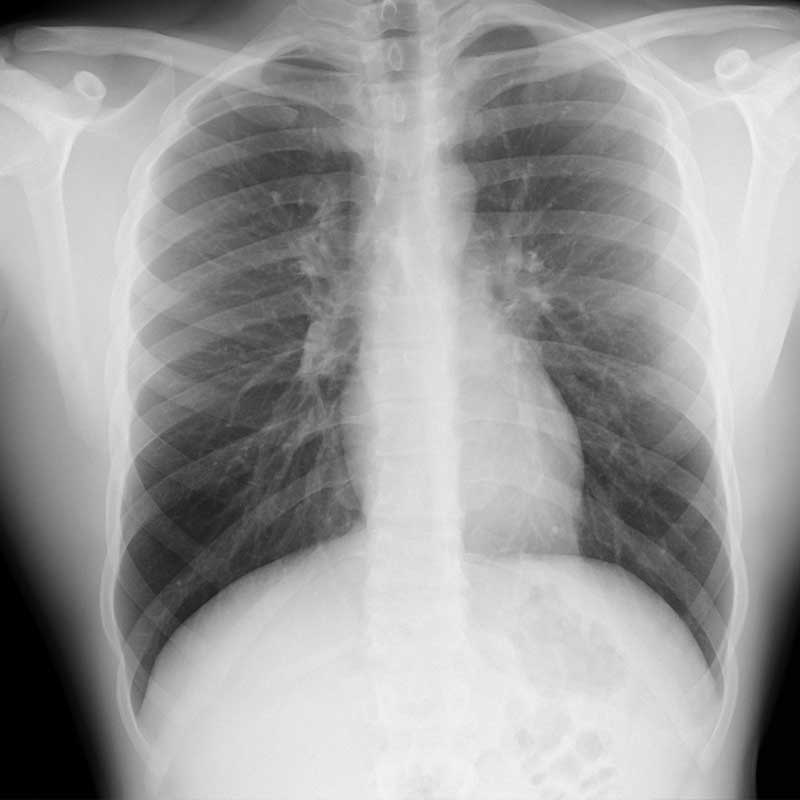

Wir versorgen die ambulanten und stationären Patientinnen und Patienten des Evangelischen Krankenhauses Göttingen-Weende an seinen Standorten mit modernsten bildgebenden Verfahren. Hierzu nutzen wir das gesamte Spektrum der radiologischen Diagnostik – volldigitales Röntgen, Durchleuchtung sowie Sonographie, Computertomographie (CT), Kernspintomographie (MRT) und Digitale Subtraktionsangiographie (DSA). Wir kooperieren eng mit unseren klinischen Fachbereichen und den Kliniken der Universitätsmedizin Göttingen. Zusätzlich sind wir bundesweit mit einer Vielzahl externer Spezialistinnen und Spezialisten vernetzt.

• Thoraxradiologie: Prof. C. Engelke